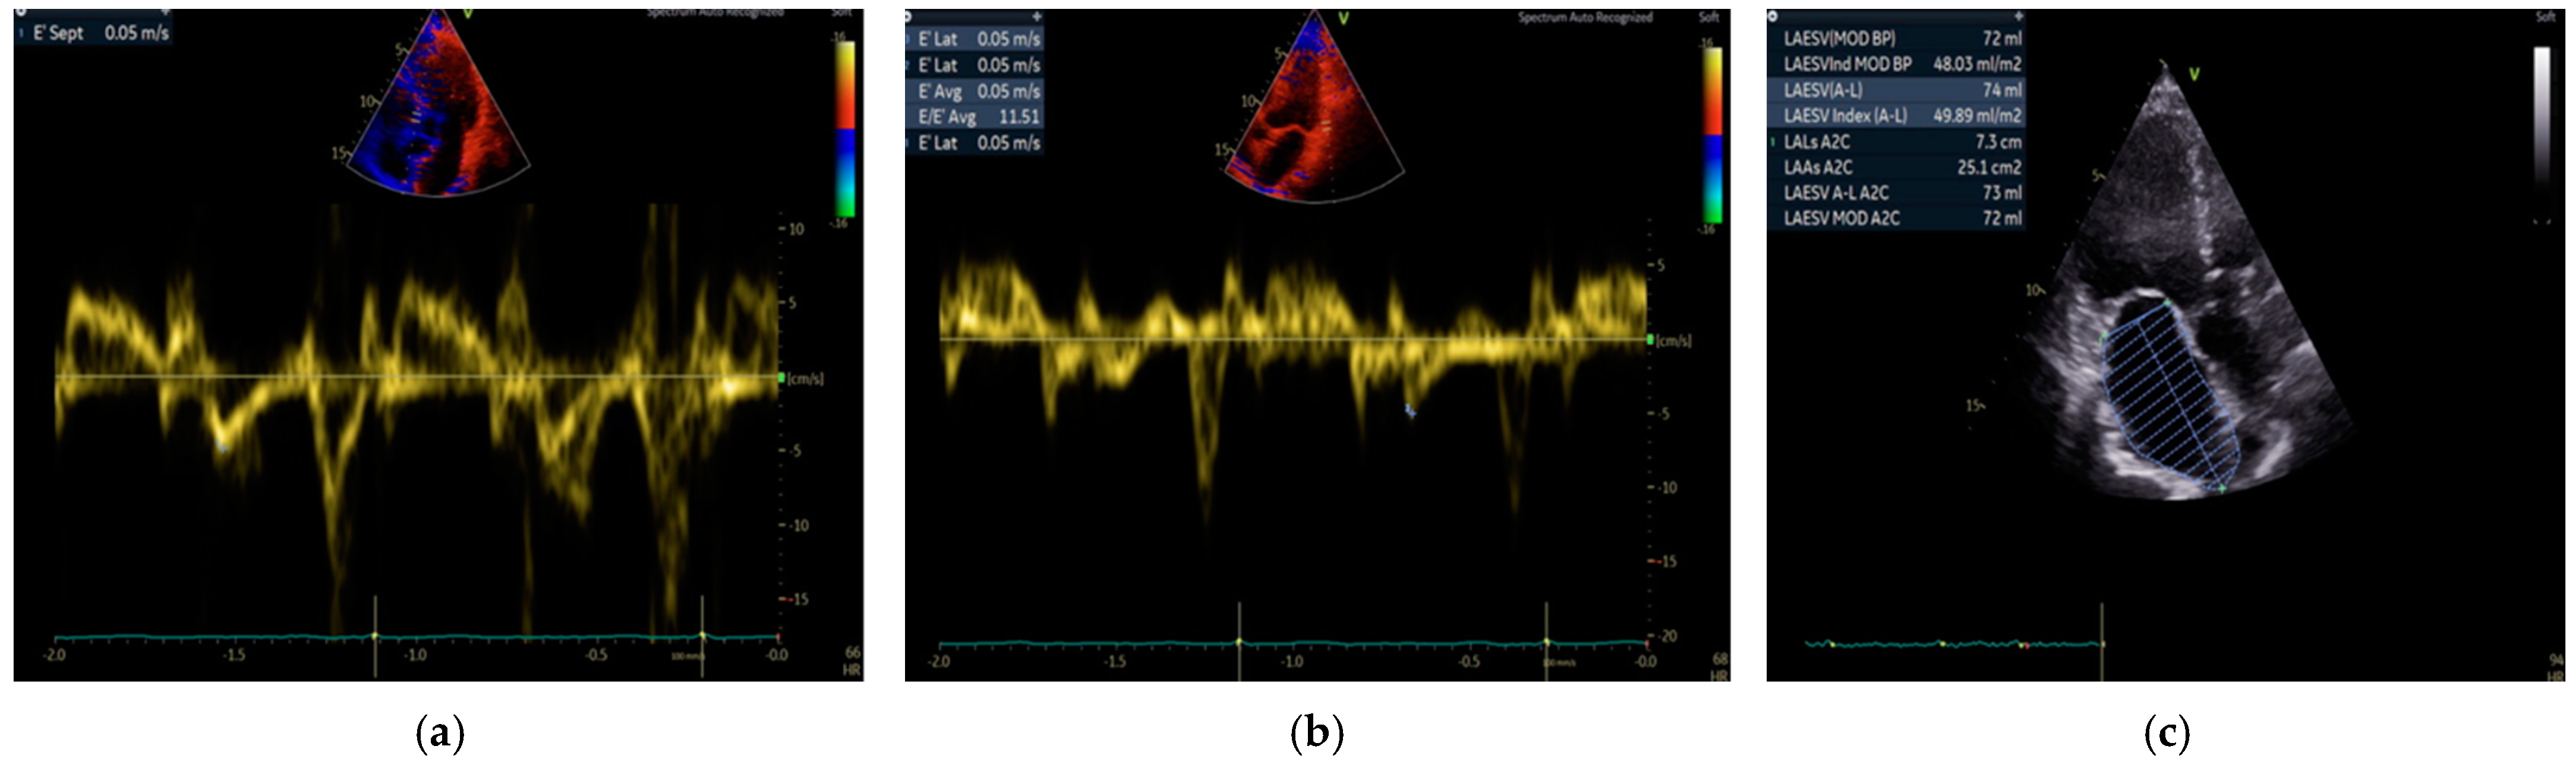

| Septal e’ (m/s) (median (Q1–Q3)) | 0.06 (0.05–0.07) | 0.07 (0.06–0.08) | 0.018 * |

| Lateral e’ (m/s) (median (Q1–Q3)) | 0.07 (0.06–0.09) | 0.08 (0.06–0.09) | 0.53 |

| LAVI (mL/m2) (median (Q1–Q3)) | 26.2 (22–35.4) | 25.4 (19.3–32.4) | 0.462 |

| Echocardiographic criteria for HFpEF (n (%)) (septal < 0.07 m/s + lateral < 0.10 m/s + LAVI > 34 mL/m2) | 6 (21) | 1 (2) | 0.006 * |